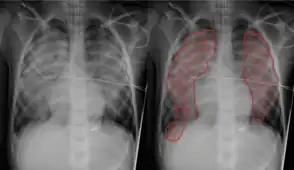

| Pulmonary edema with small pleural effusions on both sides | |

Chest X-ray has been used for many years to diagnose pulmonary edema due to its wide availability and relatively cheap cost.[4] A chest X-ray will show fluid in the alveolar walls, Kerley B lines, increased vascular shadowing in a classical batwing peri-hilum pattern, upper lobe diversion (biased blood flow to the superior parts instead of inferior parts of the lung), and possibly pleural effusions. In contrast, patchy alveolar infiltrates are more typically associated with noncardiogenic edema.[3]